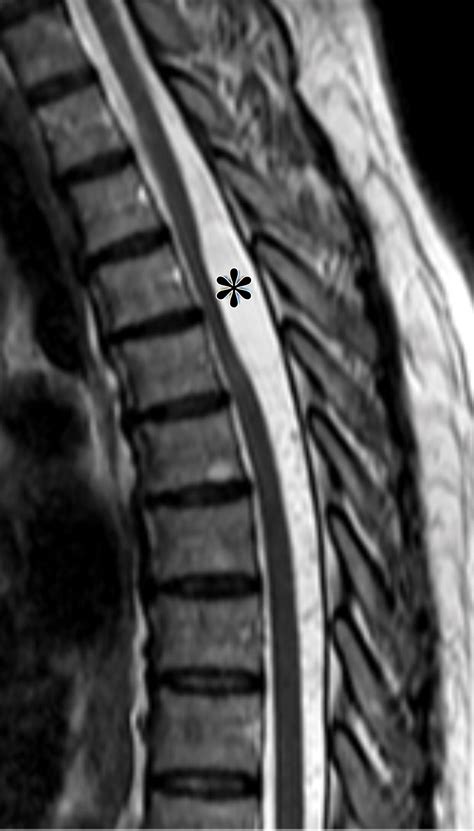

First off, what exactly is a myelogram? It's a specialized diagnostic imaging procedure used to examine the spinal canal. Doctors use it to look at the spinal cord, nerve roots, and other structures to identify problems like herniated discs, spinal stenosis, tumors, or inflammation. During the procedure, a special contrast dye is injected into the spinal fluid, making these structures visible on X-ray, CT scans, or sometimes MRI.